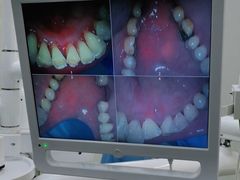

• 牙博士口腔品牌连锁(杨浦店)

• -牙博士口腔品牌连锁(杨浦店)

空空酱 | 21-03-18